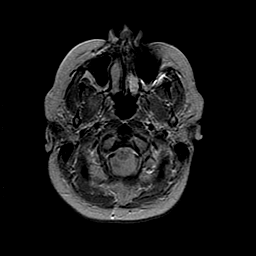

MR Study #2 -- Slice #6